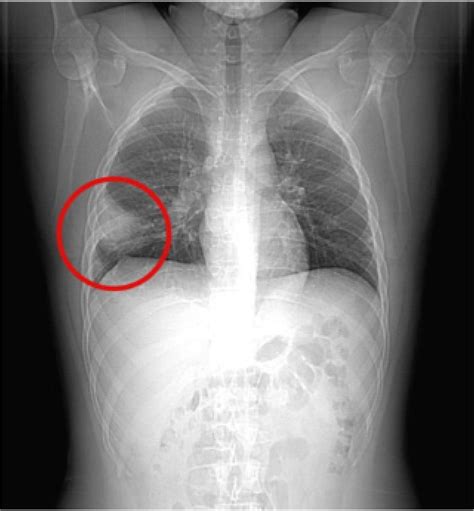

An X-ray is a common imaging technique used to visualize the internal structures of the body. In the context of a lung embolism, a Lung Embolism X Ray can provide valuable information about the condition of the lungs and the presence of any blockages. However, it is important to note that while an X-ray can help rule out other conditions, it is not always sufficient to confirm a lung embolism on its own.

When a lung embolism is suspected, a Lung Embolism X Ray may reveal:

• Enlarged pulmonary arteries

• Pleural effusion (fluid around the lungs)

• Atelectasis (collapse of lung tissue)

• Pneumonia or other lung infections

However, these findings are not specific to a lung embolism and can be seen in other conditions as well. Therefore, additional diagnostic tests, such as a CT scan or a ventilation/perfusion (V/Q) scan, are often required to confirm the diagnosis.

Chest X-Ray

A Lung Embolism X Ray is often the first imaging test performed. It can help rule out other conditions that may cause similar symptoms, such as pneumonia or a collapsed lung. However, as mentioned earlier, a chest X-ray alone is not sufficient to confirm a lung embolism.